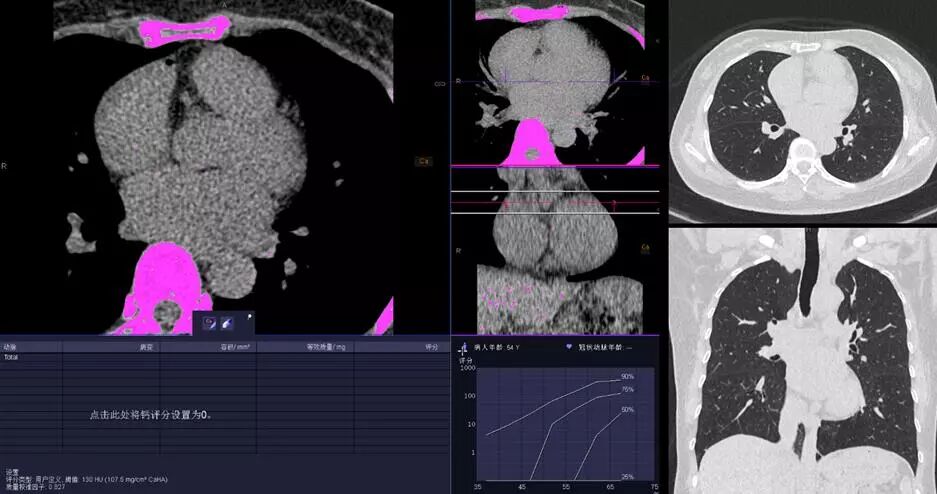

△KV純譜技術(shù)高端體檢一站式體檢——鈣化積分+肺一站式檢查

△66ms單扇區(qū)時間分辨率,任意心率、節(jié)律高清成像